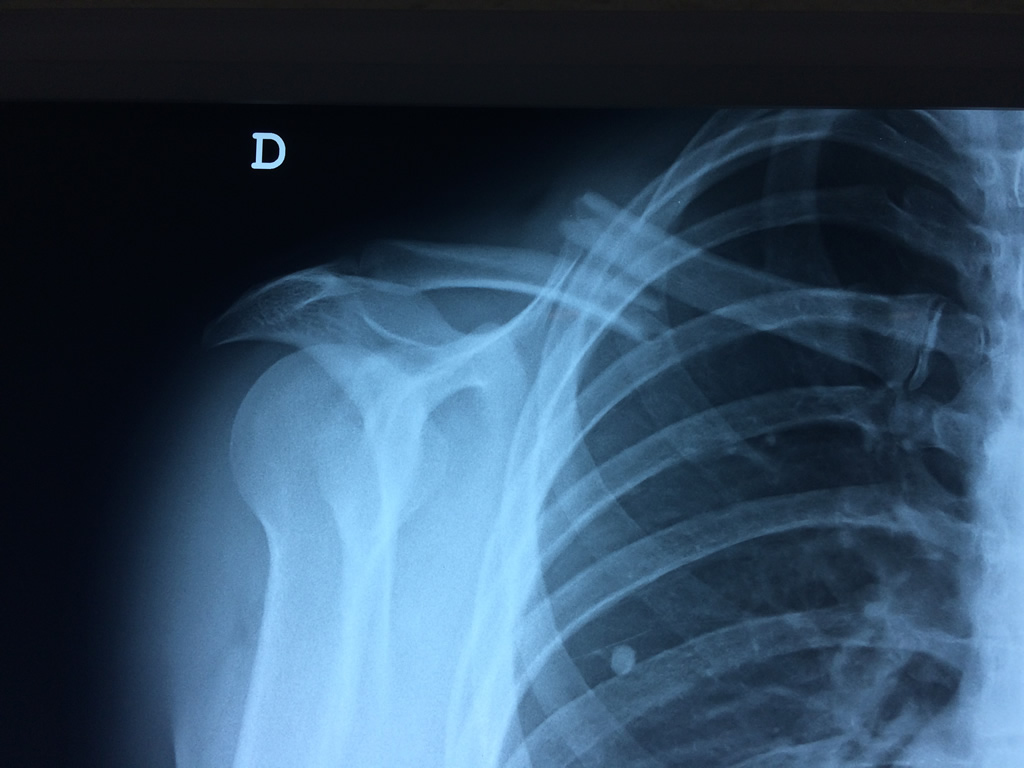

Cirugías de Hombros - Clavícula

La clavícula es un hueso largo, con forma de "S" itálica, situado en la parte anterosuperior del tórax. Junto con la escápula forman la cintura escapular. Se puede palpar por toda su longitud y se extiende del esternón al acromion de la escápula, siguiendo una dirección oblicua lateral y posterior.